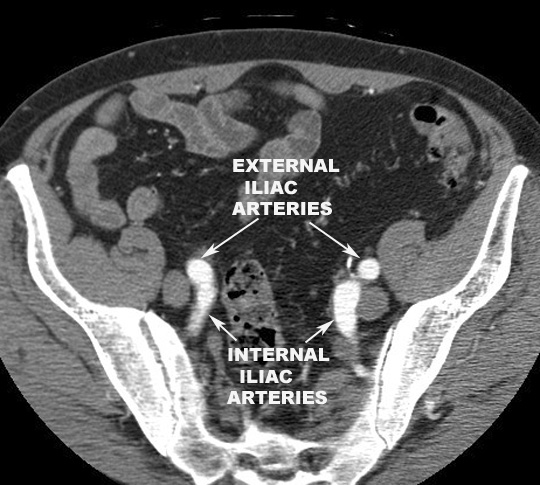

- The common iliac artery ends by dividing

into

- Internal iliac artery

- External iliac artery